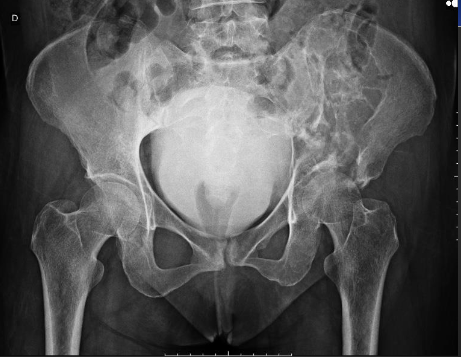

Plamacytoma Pelvic view on X-ray